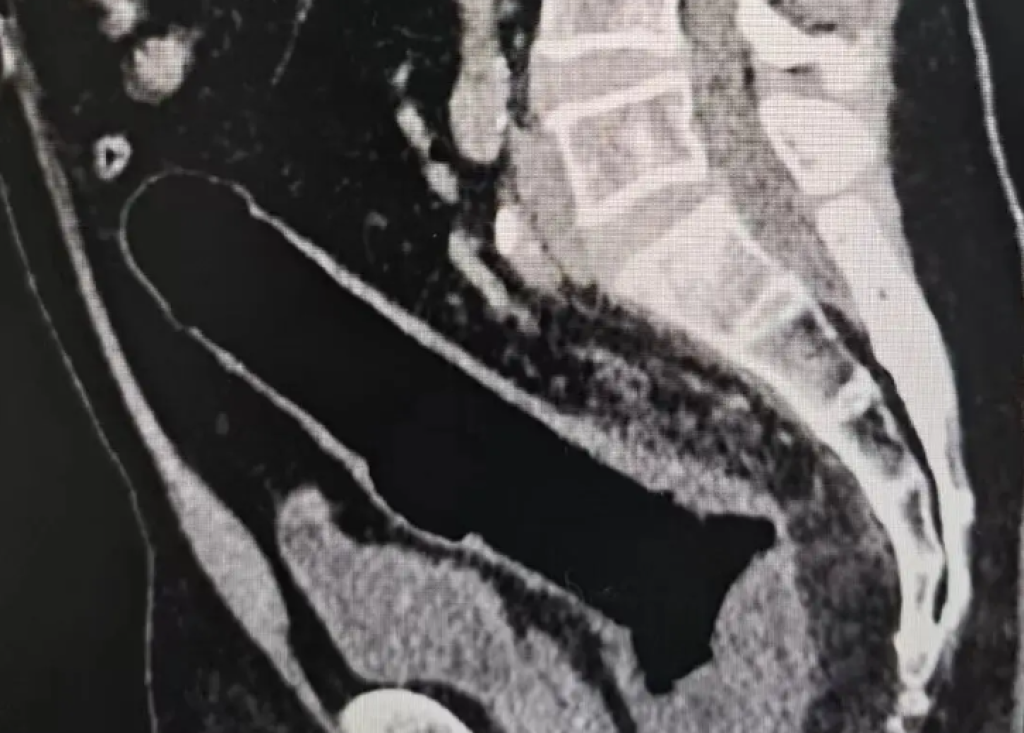

誰知兩三天過去,異物不僅沒有排出,患者還出現了明顯腹痛。再次就醫做斷層掃瞄檢查後,結果顯示腸道已經穿孔,原本簡單的異物取出問題,徹底演變成了急症。